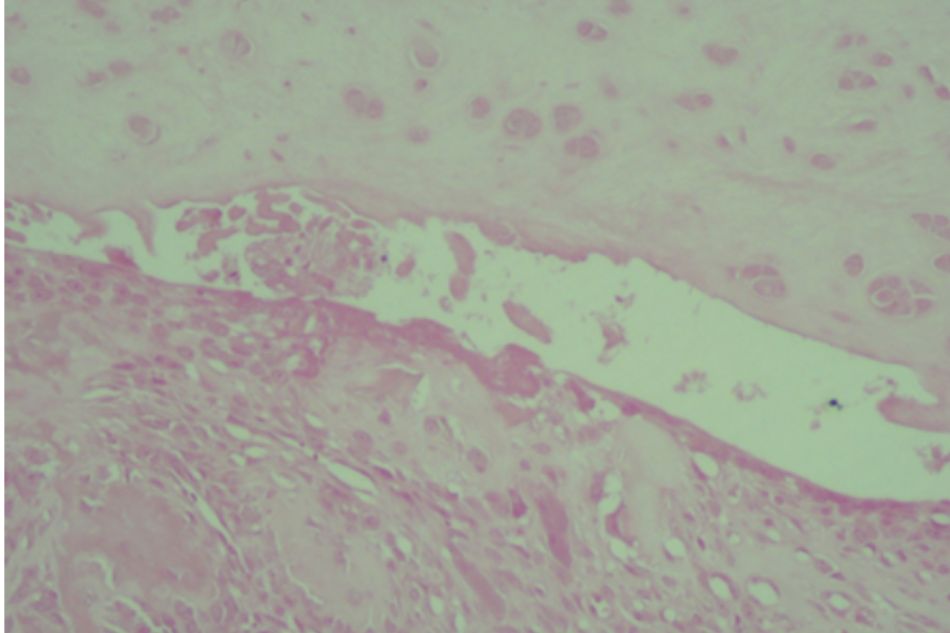

Figure 2.5. Knee joint sample in Group III (rat no.21)

Mild subchondral bone and cartilage damage

Figure 2.6. Knee joint sample in Group III (rat no.22)